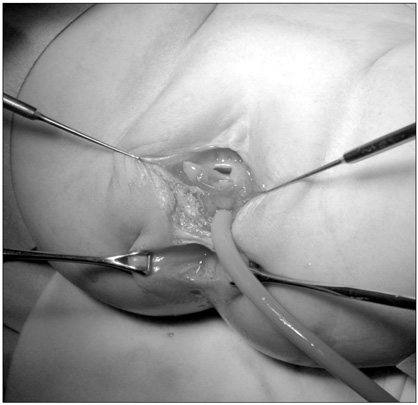

Fig. 1). Under general anesthesia, a small opening located posterior to and near the vagina at vestibule was found. The structure that had been misdiagnosed as a fistula based on the colon study was not present. The patient had a normally sited anus, an anterior ectopic anus, and a double vagina (

Fig. 2). A catheter was inserted through the ectopic anus, and an intraoperative contrast study and sigmoidoscopy were performed. A parallel tubular duplication with a common wall was found. The common wall extended 5 cm from the anal verge to the sigmoid colon and then 20 cm to the level of the proximal sigmoid colon. Proximally, the anterior duplication and normal colon merged and formed a normal colon. Because most of the stool moved through the anterior duplication and because the diameter of the anterior duplication was larger than that of the normally located colon (

Fig. 2Examination under general anesthesia revealed a normal anus, an anterior anorectal duplication (catheter-inserted state), and duplicate vaginal openings.